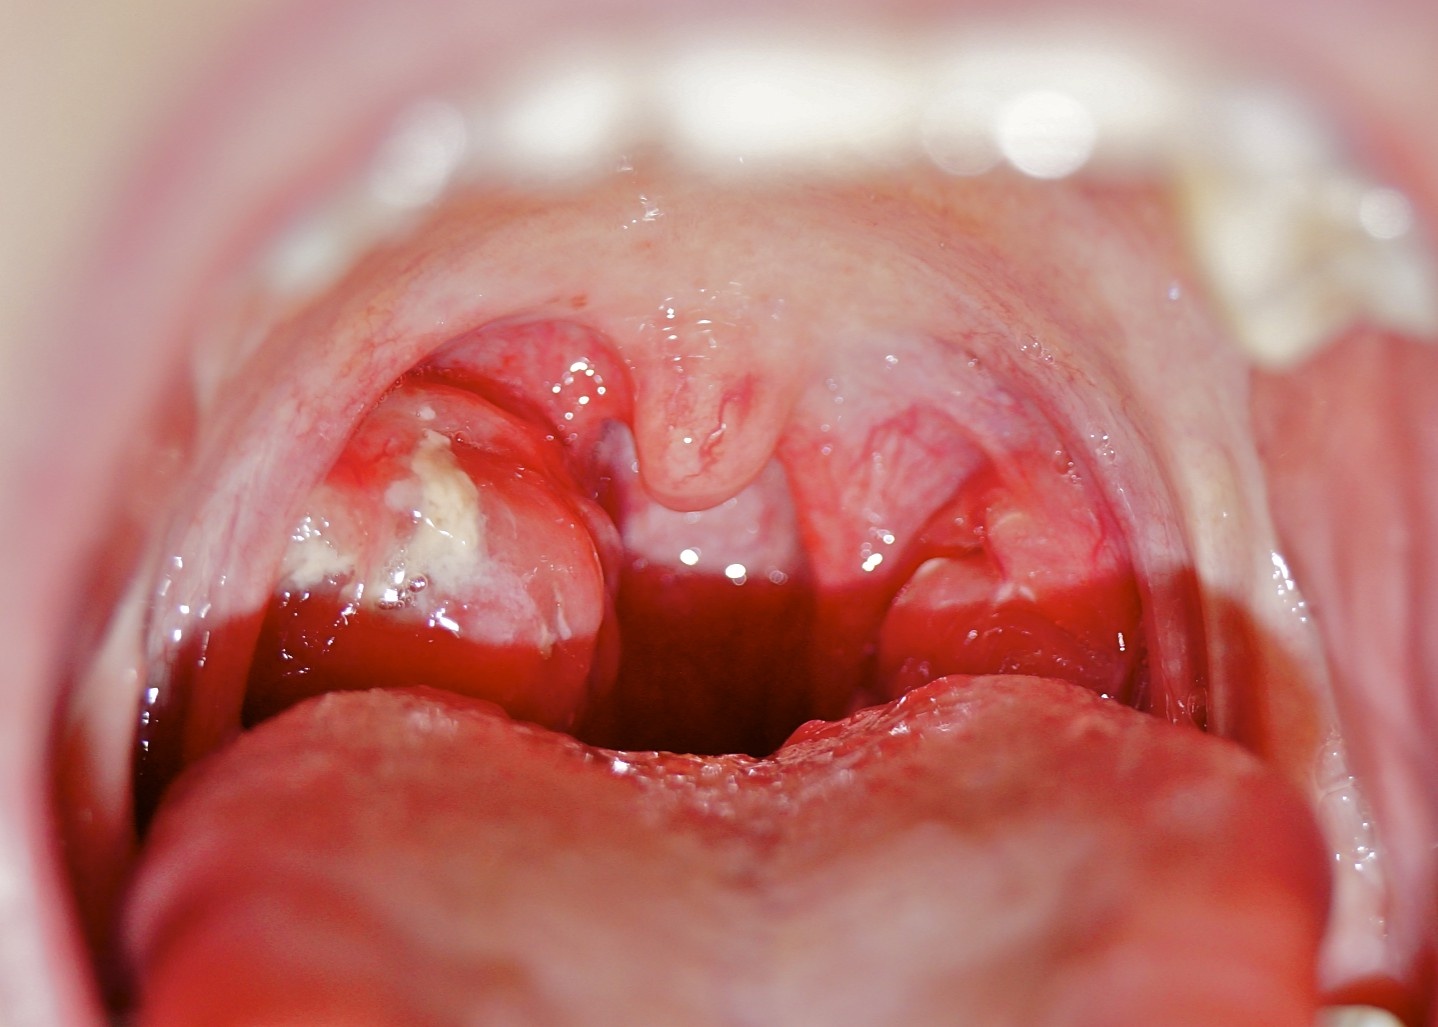

Theo bác sĩ, nếu trẻ bị sốt cao 38-40 độ C, người mệt mỏi, trong họng có mủ bẩn ở khe, hốc amidan hai bên, nhiều khả năng trẻ đã bị viêm họng.

Đối với bé trên 6 tháng tuổi bị sốt ở mức 39 độ C, họng có dấu hiệu bất thường như sưng, tấy đỏ, không thể mở miệng vì đau, hơi thở khó nhọc, ăn (bú) kém, quấy khóc liên tục, cần nhanh chóng hạ sốt an toàn và đưa bé đi khám ngay lập tức.

| Viêm họng cấp có thể gây ra một số biến chứng như viêm cầu thận cấp, thấp tim, viêm khớp cấp. Ảnh: Seoarticlelibrary . |